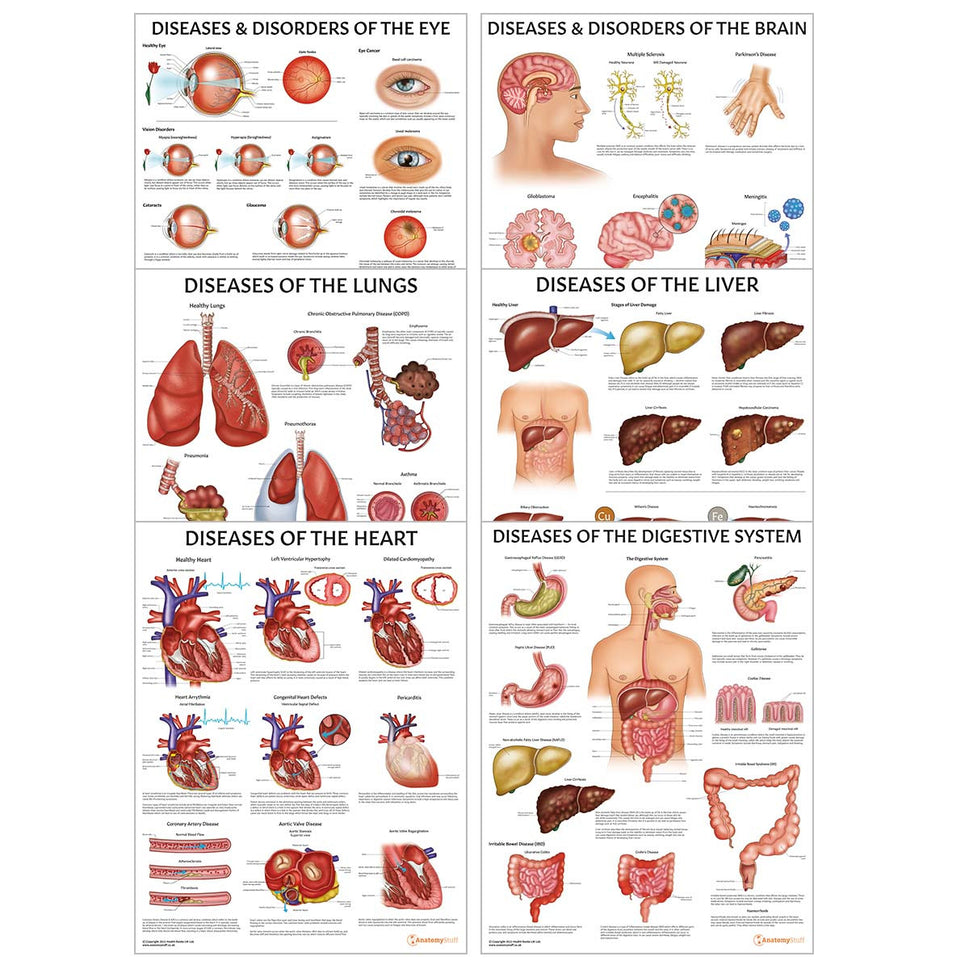

Enhance medical education with our collection of digestive system anatomical models including the stomach, liver, gallbladder, pancreas & colon models. Discover the anatomy of healthy organs as well as common gastrointestinal diseases such as stomach ulcers, gallstones and liver cirrhosis. Our digestive system anatomy posters are ideal for study and patient education.

At AnatomyStuff we stock a diverse range of digestive system anatomical models to suit your training needs. From budget models and affordable medical education posters to highly advanced 3D printed bowel models, you can transform medical training and patient education. As well as our own exclusive collection, we are proud resellers of 3B Scientific, Anatomy Lab, Denoyer-Geppert Science Company, ESP Models, Erler Zimmer and GPI Anatomicals. Explore our exclusive collection of digestive system anatomy charts, posters, fine art prints and digital anatomy study guides. Discover the anatomy of key organs like the liver, stomach, pancreas and bowel as well as the pathophysiology of common conditions like peptic ulcer disease, coeliac disease, IBD and much more. We have anatomy posters suitable for school children all the way up to medical degree level. From a liver anatomy poster to a digital study guide all about common GI disorders, find exactly what you need right here to enhance medical training and patient education.